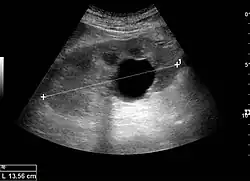

Simple renal cyst.jpg

Simple renal cyst